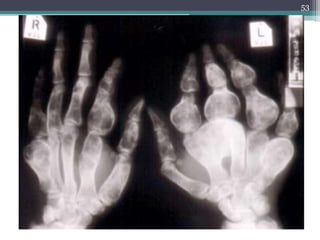

MULTIPLE CHONDROMAS IN OLLIER

DISEASE

52

53

MULTIPLE CHONDROMAS INOLLIER DISEASE 52

• 53.